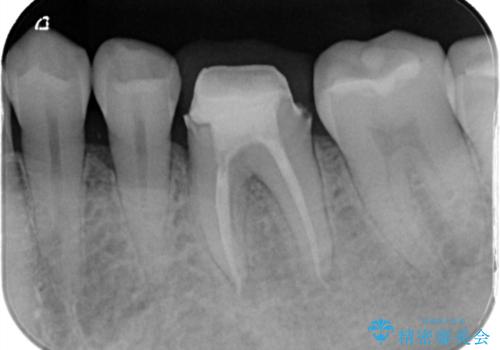

- 数年前に他医院で抜歯したままで過ごし、今回歯を入れたいとのことで来院された患者様です。

治療回数を短くしたいと1DAYインプラントを希望されました。

インプラント埋入手術は1回で全て行い、2ヶ月後にはセラミック治療で、審美回復と機能回復をしました。